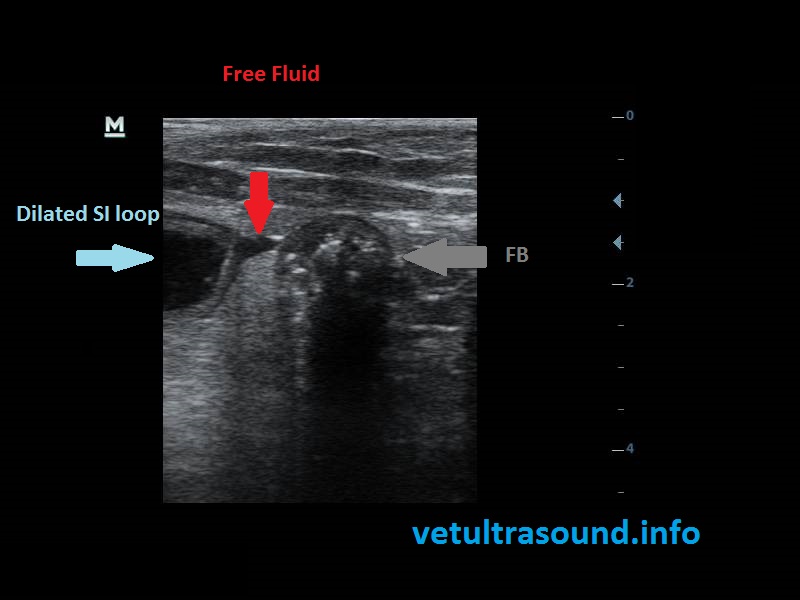

On the ultrasound, there were small intestinal loops dilated with fluid and a thickened portion of the SI was noted. In the lumen, multiple small foreign bodies were detected. There was small amount of ascites.

The foreign bodies were small plastic pieces of flip flop.